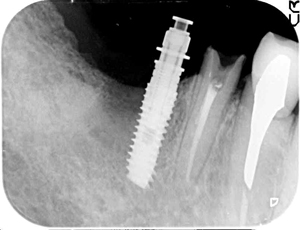

左下のレントゲン。

右上のレントゲン。